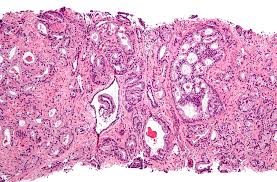

Many people have considered prostatic hypertrophy closely related

to prostate cancer. This type of manifestation, also known as BHP -

Benign Prostatic Hyperplasia, is represented by an enlarged prostate and

scientifically speaking there was no link to connect this enlarged

prostate to the apparition of prostate cancer.